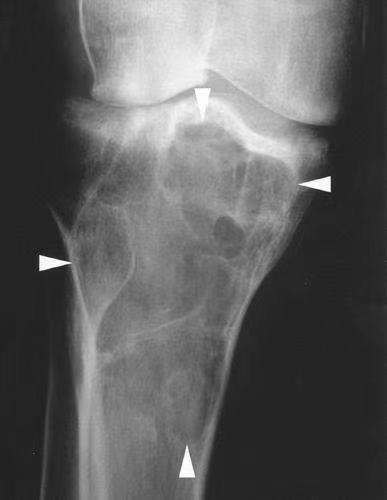

Bone tumors can form in any bone in the body, but it most commonly affects the pelvis or the long bones in the arms and legs. Benign bone tumors can grow and could compress healthy bone tissue and cause future issues. Malignant bone tumors can cause cancer to spread throughout the body.

A dull ache in the affected bone is the most common symptom of bone cancer. The pain starts off as occasional and then becomes severe and constant. The pain may be severe enough to wake you up in the night. Sometimes, when people have an undiscovered bone tumor, what seems like an insignificant injury breaks the already weakened bone, leading to severe pain. This is known as a pathologic fracture. Sometimes there may be swelling at the site of the tumor. Or you might not have any pain, but you’ll notice a new mass of tissue on some part of your body. Tumors can also cause night sweats, fevers, or both. People with benign tumors might not have any symptoms. The tumor might not be detected until an imaging scan reveals it while receiving other medical testing.

Image-guided RFA is a conventional modality for the treatment of primary and metastatic bone tumors associated with severe pain; it is also a relatively effective, minimally invasive, and safe treatment. RFA treatment reduces pain level, increases functionality, and locally suppresses the tumor in patients with bone cancer.